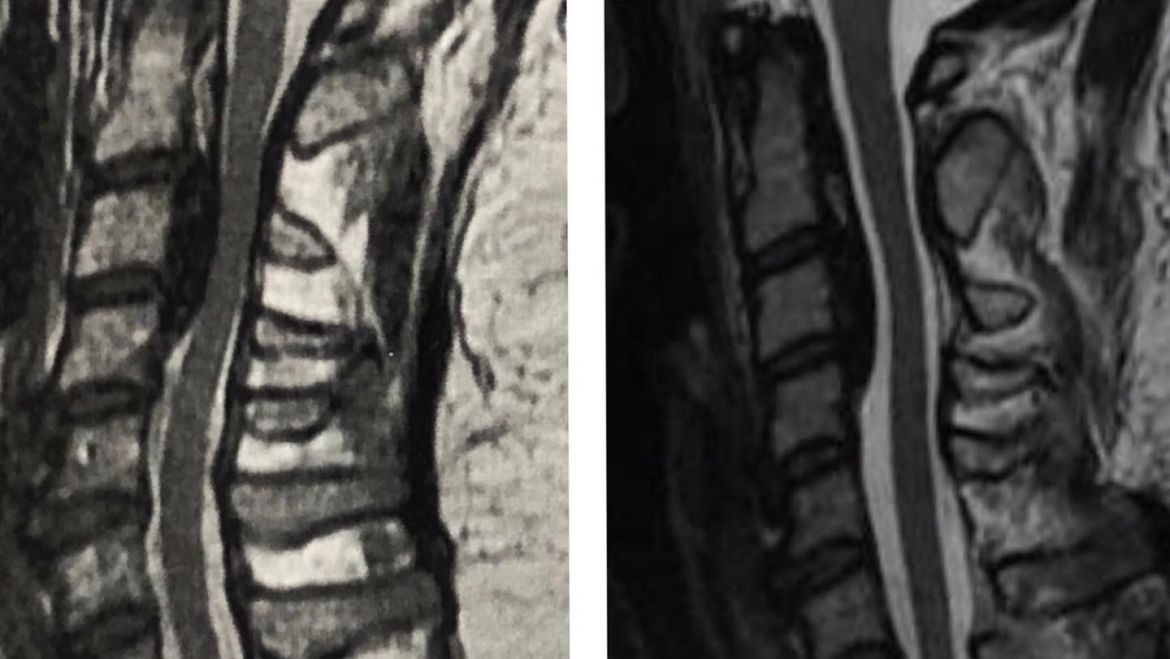

A ossificação do ligamento longitudinal posterior (OLLP) é uma doença rara no ocidente mas bem mais comum na população japonesa e asiática em geral. Nessa doença, ocorre calcificação anormal e aumento da espessura de um ligamento situado dentro do canal da coluna, causando estreitamento do mesmo. Isso pode causar compressão da medula e raízes cervicais.

Os sintomas vão desde dor cervical (cervicalgia), formigamentos, até fraqueza nos membros, perda da sensibilidade e perda do controle da urina e fezes. Em casos inicias ou sem sintomas pode ser realizado o acompanhamento clínico e com exames de imagem. Caso o paciente apresente sintomas ou haja compressão significativa da medula nos exames de imagem é indicado tratamento, que no caso é cirúrgico. especialista em coluna

O tratamento cirúrgico pode ser realizado por várias técnicas, dependendo de vários fatores, como grau de compressão, quantidade de níveis afetadas, anatomia do paciente e risco cirúrgico. No caso da imagem, foi optado por abordagem posterior com laminoplastia. Essa técnica permite descompressão adequada do canal vertebral e mantém a mobilidade do pescoço. Dessa forma é alcançada a melhora da dor cervical e o restabelecimento da função neurológica. especialista em coluna